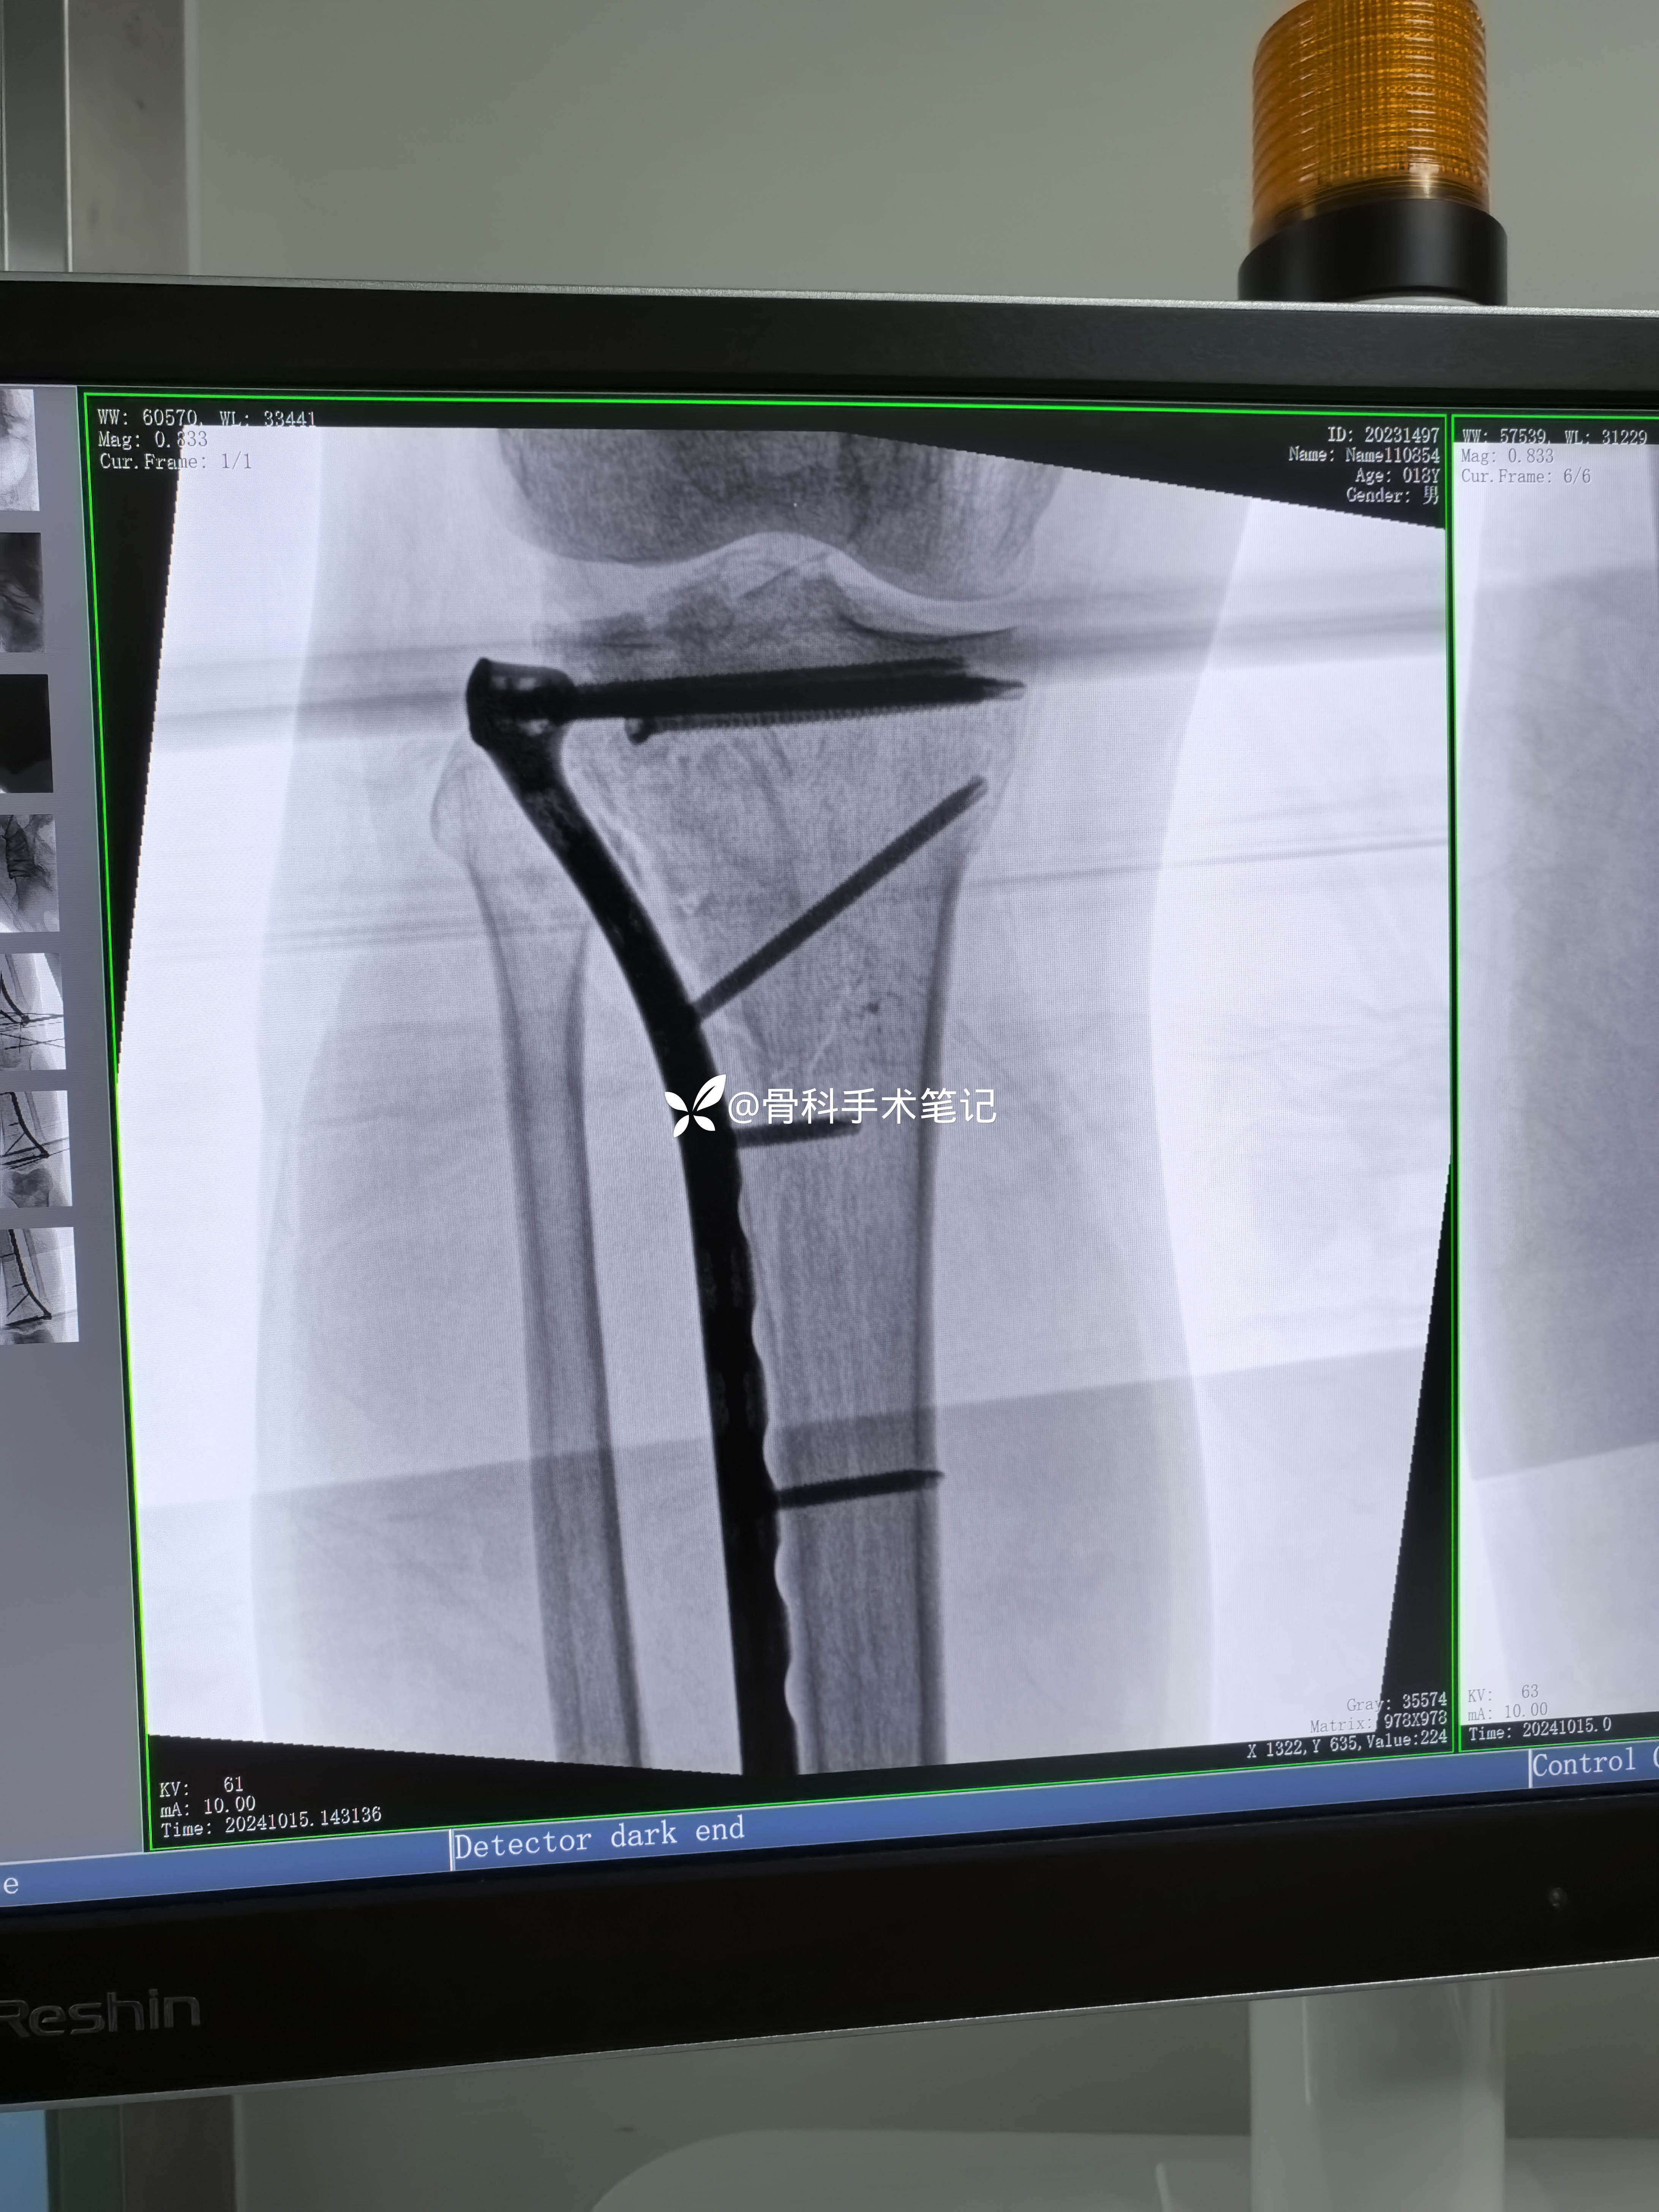

外侧切口→撑开器撑开→缝合修复外侧半月板→外侧开窗复位塌陷的关节骨块克氏针临时固定这→取髂骨植骨支撑→外侧排钉钢板固定。

术后影像资料

保留固定关节面骨块克氏针是否会更好呢!